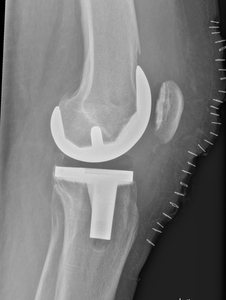

Lateralt (horisontalt)

Thumb d4doc formularer upload 2014 11 kn c3 a6 20lat 20med 20horisontal Thumb d4doc formularer upload 2014 11 kn c3 a6 20ligge 20med 20horisontal 20nr 202 Thumb d4doc formularer upload 2014 11 kn c3 a6 20lat 20allo

Lejring:

Rygleje med benet let indadroteret, således at patella er projiceret midt på femur. Læg evt. en pude under crus/knæ.

Rørkipning:

Centrering:

På femurkondylerne.

Kriterier:

Femoropatellarleddet, knæleddet og hele patella skal fremstilles. Femurkomponenten skal fremstå uden dobbeltkontur.

Bemærkning:

1. post-operative kontrol tages liggende. Det er vigtigt at alloplastikkomponenterne fremstilles optimalt, og derfor kan efterfølgende kontroller evt. tages i gennemlysning. Ved alloplastikknæ OBS sporing suppleres med axial patella.